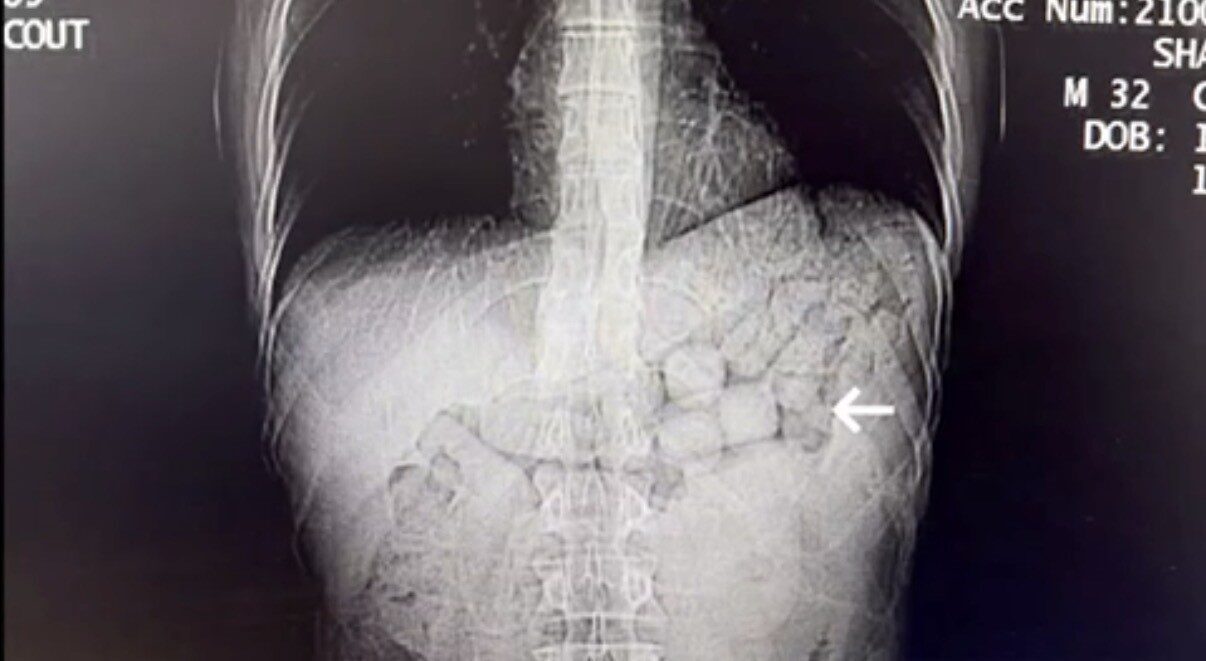

Söz konusu kişilerin çekilen tomografi görüntülerinde, mide ve bağırsak bölgelerinde yabancı cisimlere rastlandı. Yaklaşık 3 gün süren kontrollerin ardından şahıslardan 91 kapsül halinde 807,15 gram Metamfetamin maddesi ele geçirildi ve şüpheliler gözaltına alındı.